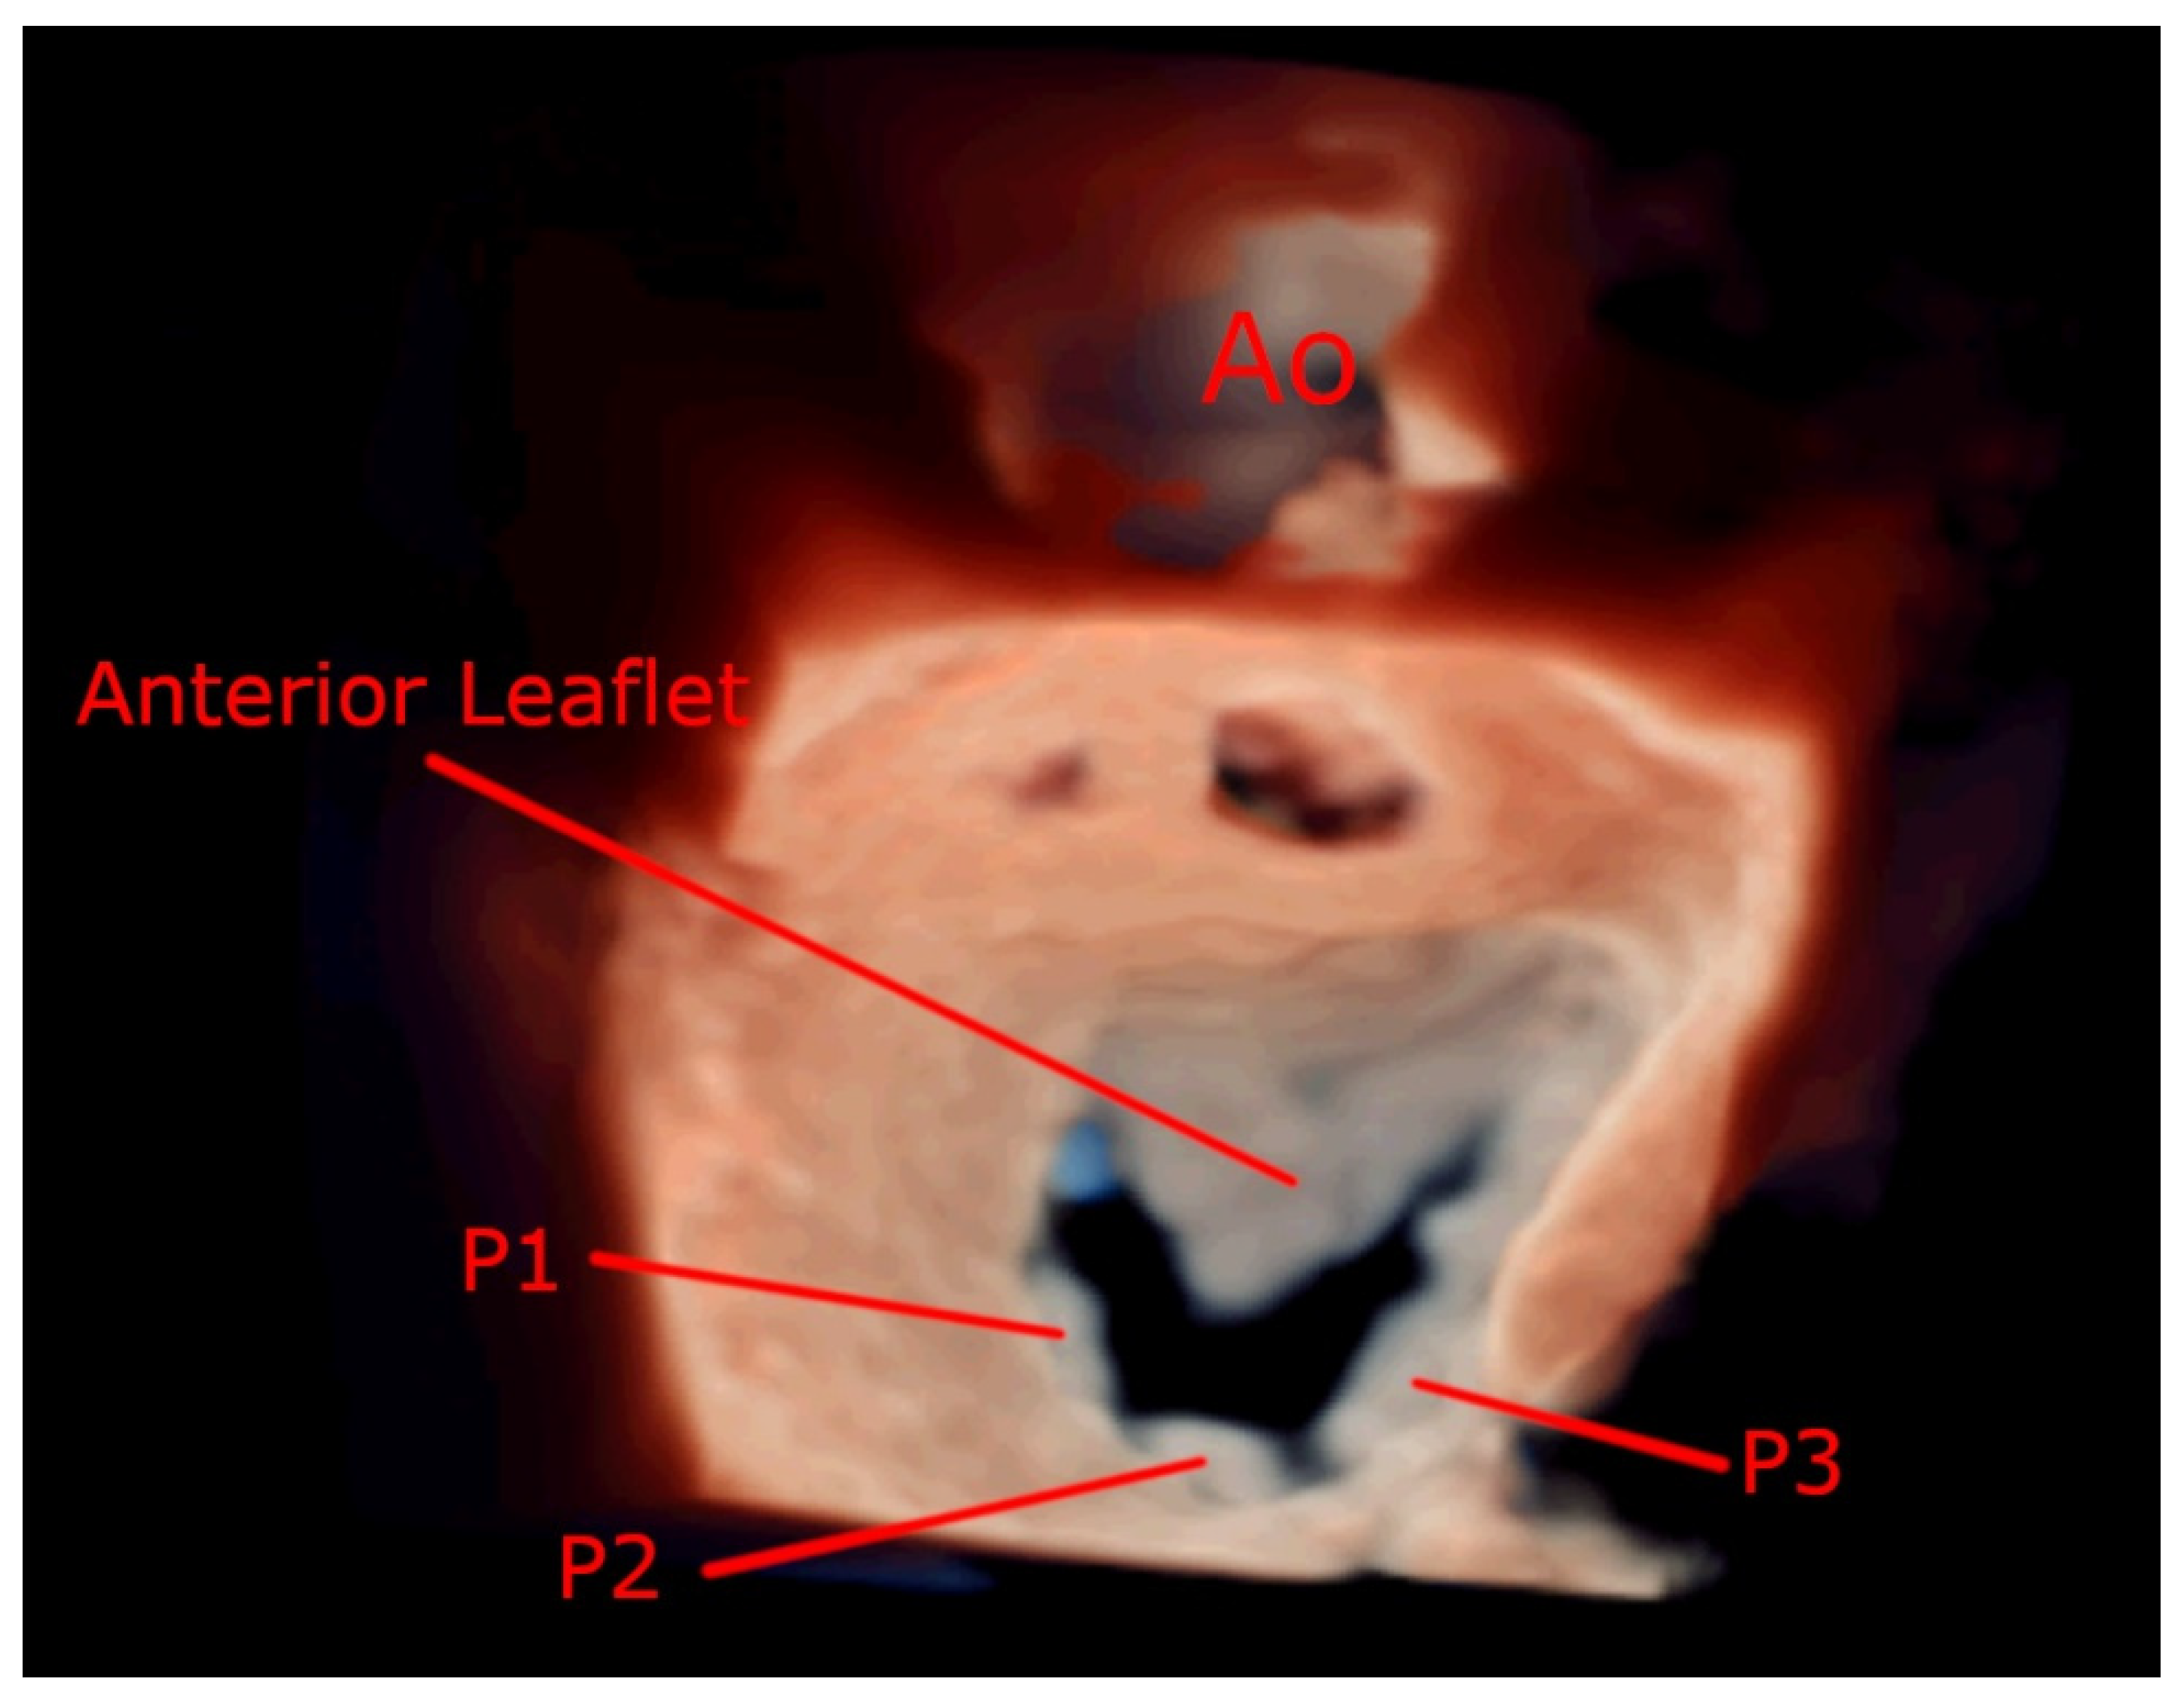

- It measures all three spatial dimensions. Therefore, it is not reliant on plane positioning and does not require geometric assumptions of cardiac structures.

- Images can be rotated and viewed from different perspectives. This allows for a better understanding of the relationship between structures and makes 3D images more intuitive.

7.4. Focused Wide-Sector (3D Zoom) Imaging

7.5. Assessment of Feasibility of Percutaneous Mitral Commissurotomy Using 3D Echocardiography